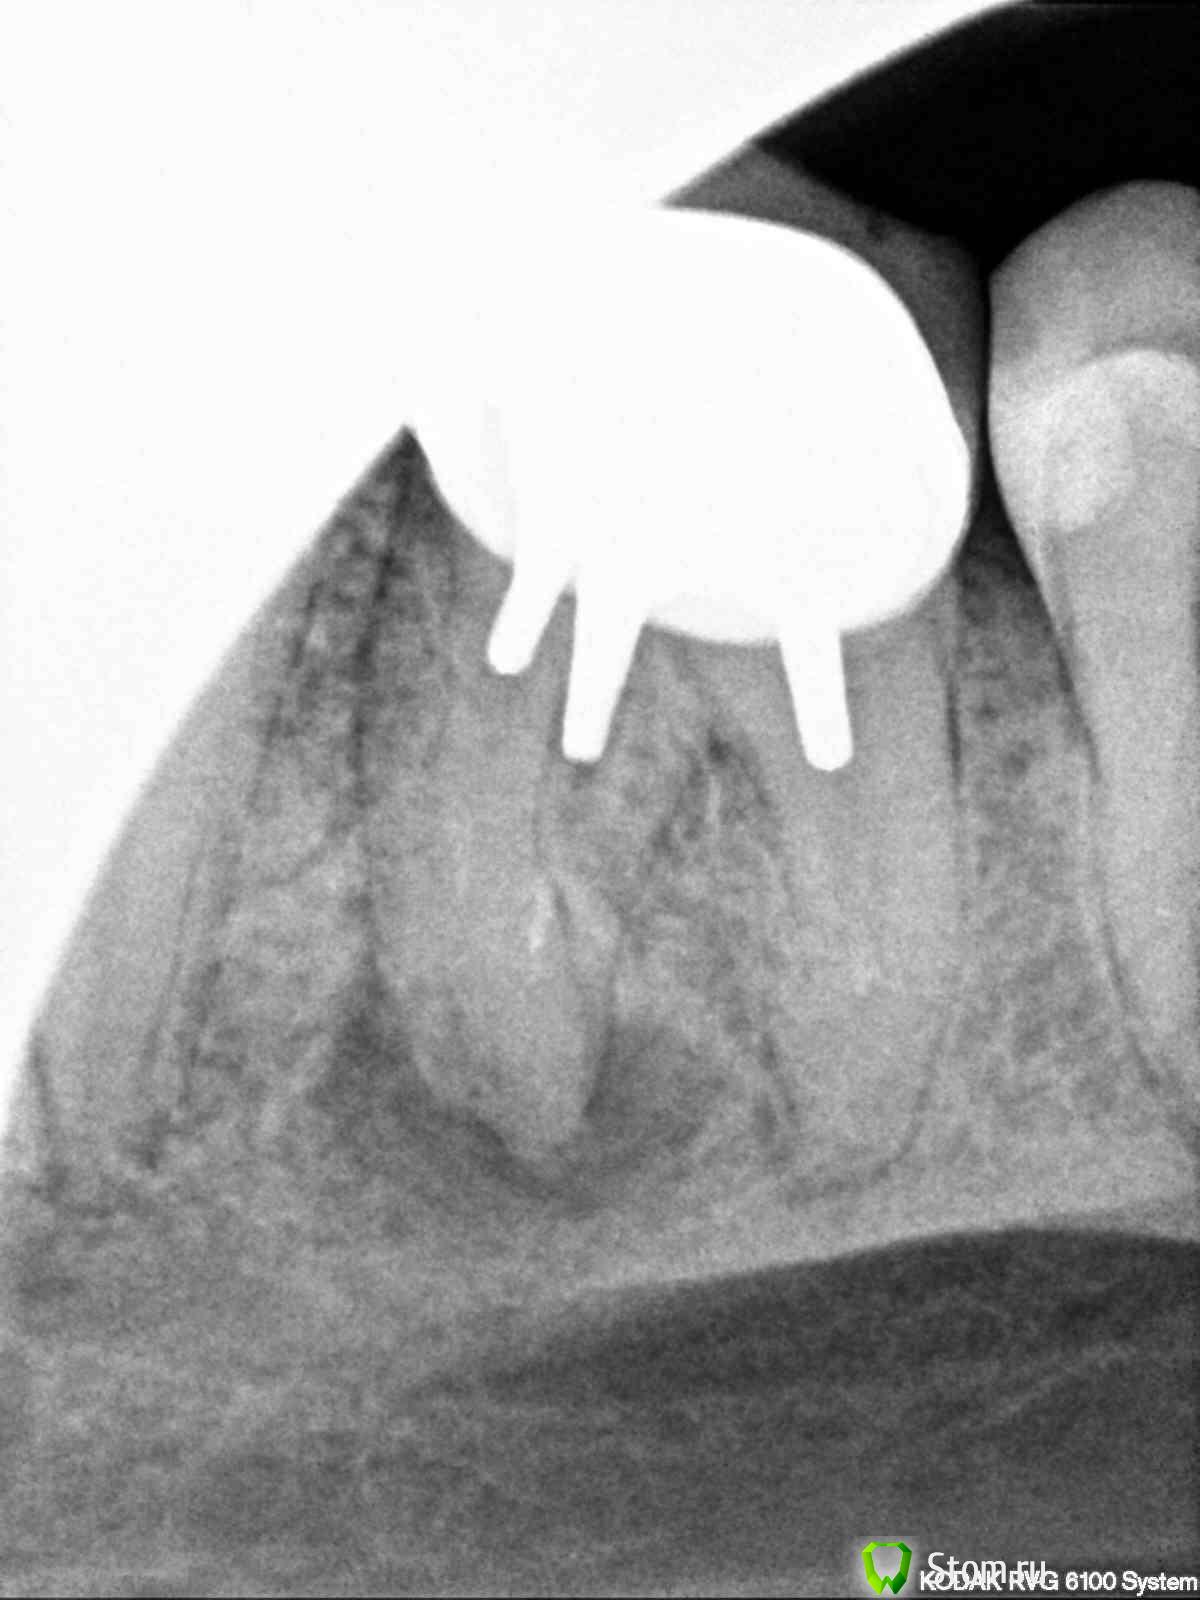

tuwaki Опубликовано 16 марта, 2012 Поделиться Опубликовано 16 марта, 2012 Здравствуйте.У меня на нижней шестерке стоит коронка. Из-за воспаления у корня зуб иногда при переохлаждении побаливает. Так уже продолжается около 5-7 лет.Сейчас доктор рекомендует мне его удалить и поставить имплант. На вопрос об альтернативе импланта было сказано, что можно попробовать сделать надрез, все зачистить и ЕСЛИ все пройдет хорошо - зуб сохранится.Помогите определиться: идти ли на такую операцию или сразу ставить имплант? Может есть еще вариант лечения? Ссылка на комментарий

Doc Опубликовано 16 марта, 2012 Поделиться Опубликовано 16 марта, 2012 Альтернативный вариант приведет только к еще большей потере кости, которая очень нужна для имплантации. Надежнее будет удалить и поставить имплантат. Ссылка на комментарий